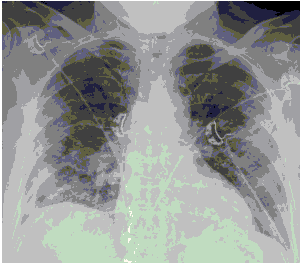

Стандартная РГ имеет низкую чувствительность в выявлении начальных изменений в первые дни заболевания и не может применяться для ранней диагностики. Информативность РГ повышается с увеличением длительности течения пневмонии. Рентгенография с использованием передвижных (палатных) аппаратов является основным методом лучевой диагностики патологии ОГК в ОРИТ. Применение передвижного (палатного) аппарата оправдано и для проведения обычных РГ исследований в рентгеновском кабинете. В стационарных условиях относительным преимуществом РГ в сравнении с КТ являются большая пропускная способность. Метод позволяет уверенно выявлять тяжелые формы пневмоний и отек легких различной природы, которые требуют госпитализации, в том числе направления в ОРИТ.

КТ имеет высокую чувствительность в выявлении изменений в легких, характерных для COVID-19. Применение КТ целесообразно для первичной оценки состояния ОГК у пациентов с тяжелыми прогрессирующими формами заболевания, а также для дифференциальной диагностики выявленных изменений и оценки динамики процесса. КТ позволяет выявить характерные изменения в легких у пациентов с COVID-19 еще до появления положительных лабораторных тестов на инфекцию с помощью МАНК. В то же время, КТ выявляет изменения легких у значительного числа пациентов с бессимптомной и легкой формами заболевания, которым не требуется госпитализация. Результаты КТ в этих случаях не влияют на тактику лечения и прогноз заболевания при наличии лабораторного подтверждения COVID-19. Поэтому массовое применение КТ для скрининга асимптомных и легких форм болезни не рекомендуется. При первичном обращении пациента с подозрением на COVID-19 рекомендуется назначать КТ только при наличии клинических и инструментальных признаков дыхательной недостаточности (SpO2 < 95%, ЧДД > 22).